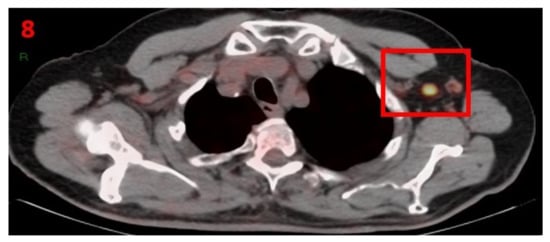

3.8. Case No 8

| Case no.8 | Prostate cancer | Left arm | 9 days | Hypermetabolic uptake in the left axillary region and lymphadenopathy | Second vaccine | 8 mm | 5 | Pfizer-BioNTech |